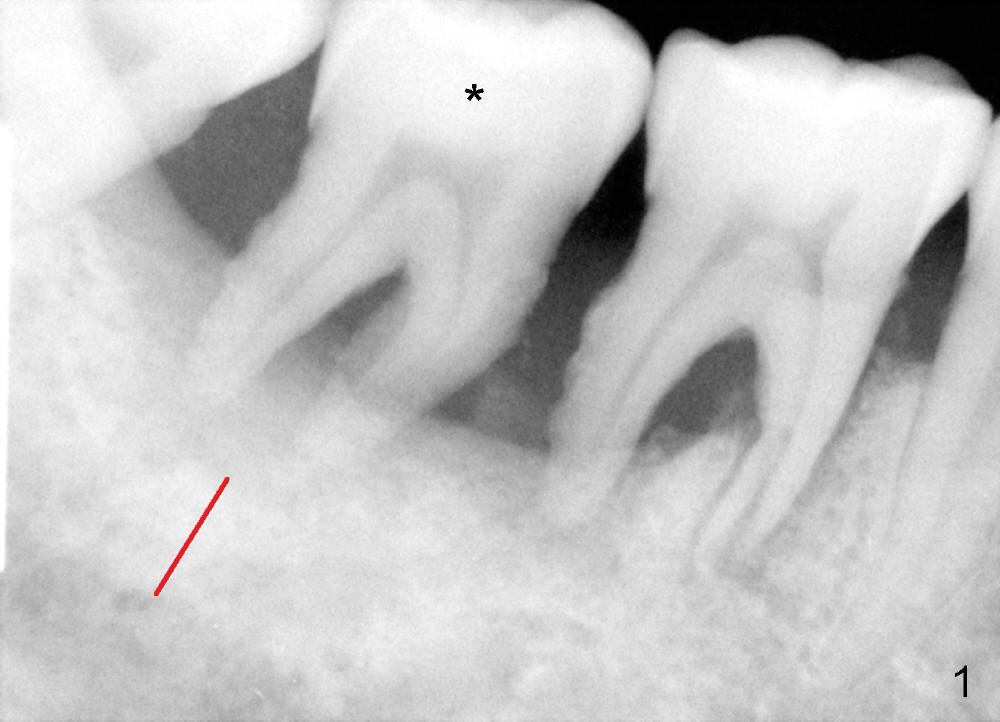

Intraop PA with a radiopaque instrument in the socket reveal the socket is large (Fig.2 arrows). The latter is filled with bone graft (Fig.3 arrows) and collagen plug (Fig.4). Fig.5 and 6 show wound healing 7 and 13 days postop. The ridge is not atrophic 4 months postop (Fig.7), ready for implant.